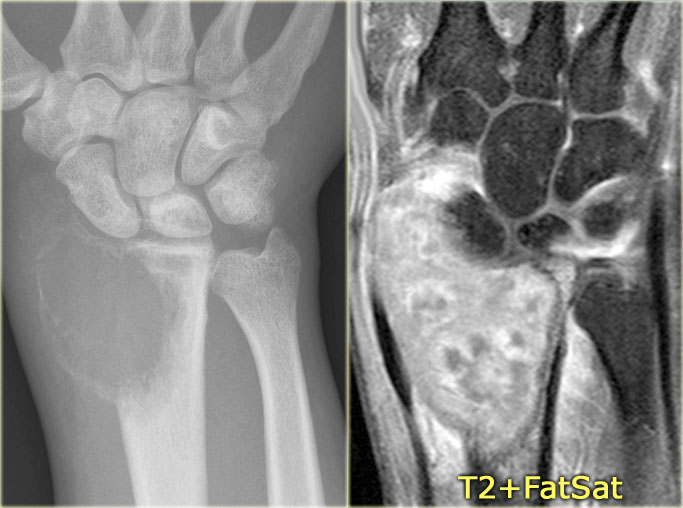

Giant cell tumor (3)

On the left a typical giant cell tumor of the distal radius.

Notice the aggressive appearance with ill-defined borders, extension to the soft tissues and destruction of subchondral bone plate.

The localisation in the epiphysis and metaphysis is in favor of diagnosis of GCT.

On the right a coronal T1-weighted CE image.

There is diffuse heterogeneous enhancement, and extension to the radiocarpal joint and surrounding edema in bone and soft tissues.